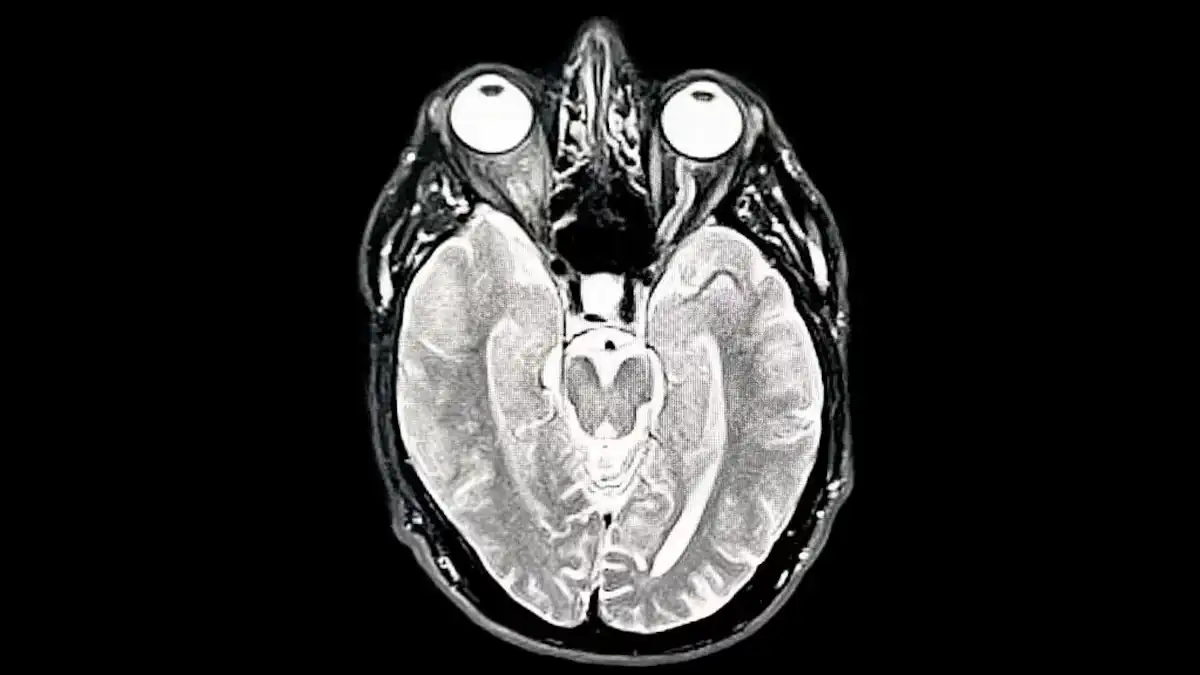

Adolescencia extendida (9 – 32 años):

Aquí ocurre el ajuste más drástico. El sistema nervioso afina sus circuitos, elimina lo que no necesita y alcanza su punto máximo de rendimiento. Es la etapa más exigente y la que impulsa el mayor salto en capacidad cognitiva.